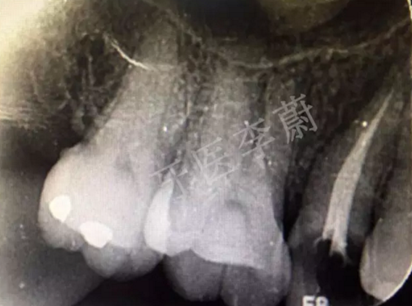

15牙根管充填術(shù)后X牙片